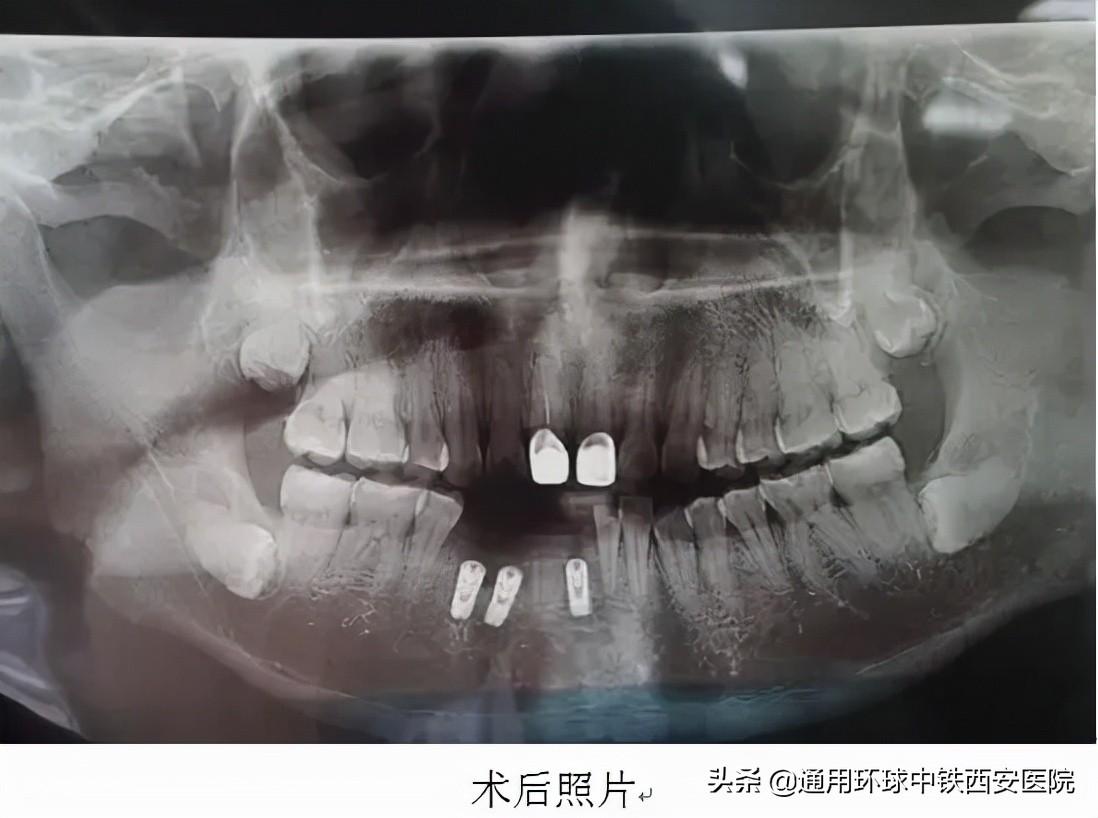

手術(shù)于9月22日進(jìn)行,術(shù)前常規(guī)消毒鋪巾麻醉,微創(chuàng)拔除41、42、44牙殘根,在與術(shù)前規(guī)劃一致的位置分別植入直徑3.75mm,高度11.5mm、直徑4.2mm,高度11.5mm、直徑4.6mm,高度10mm的種植體,在唇側(cè)植入骨粉共0.25g。修整外形后。表面覆蓋可吸收生物膜,間斷嚴(yán)密縫合傷口。手術(shù)歷時約40分鐘,術(shù)后宋先生無不適。